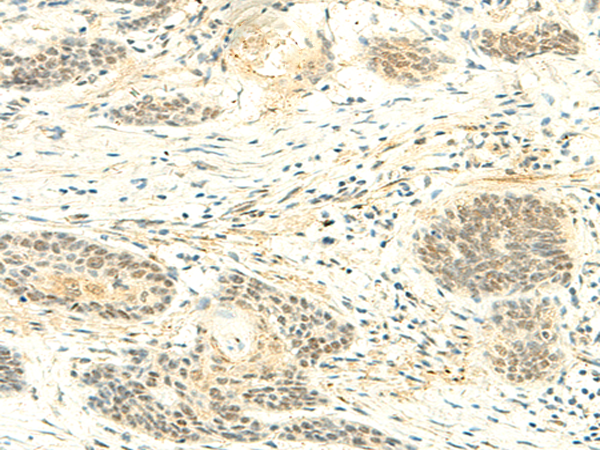

分类: 科研抗体货号: P09929别名:应用: IHC反应种属: Human